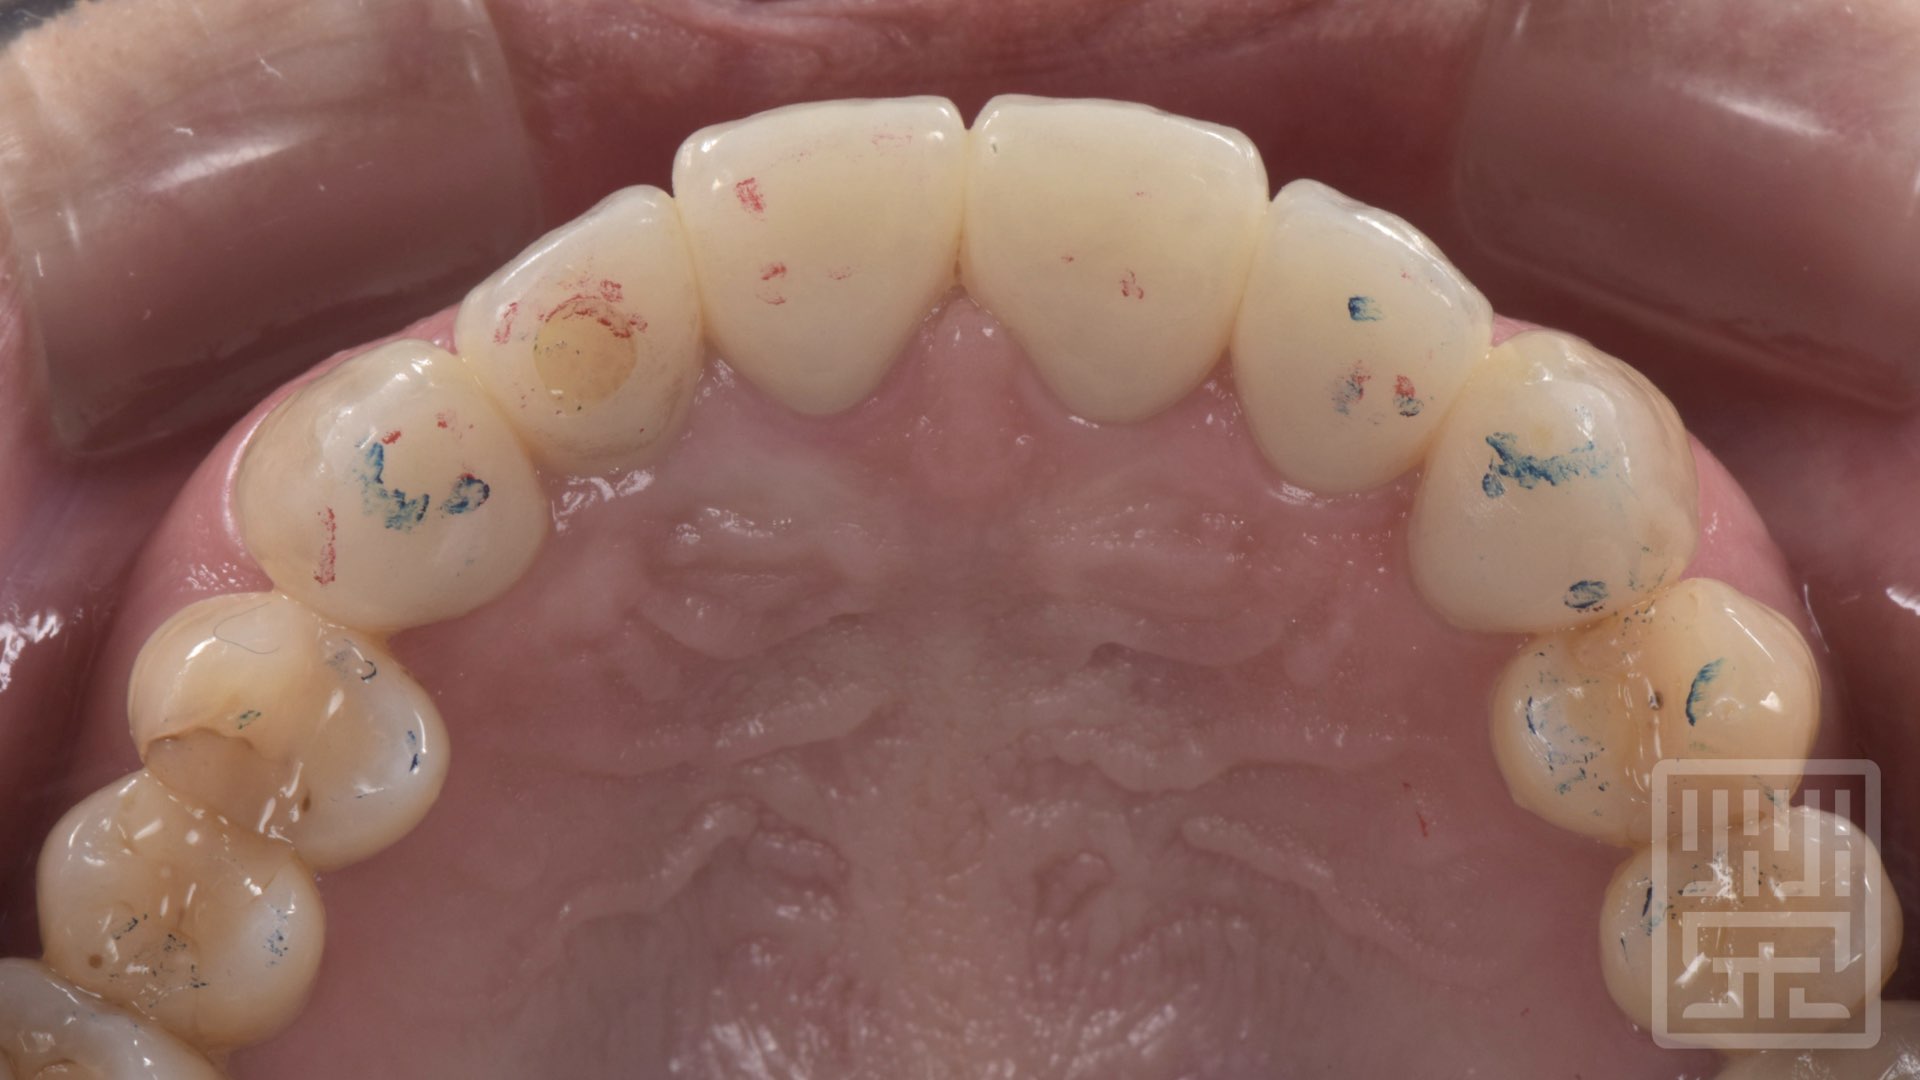

保護性咬合痕跡

植牙全瓷冠